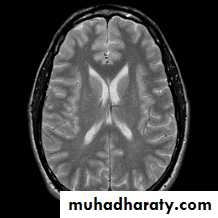

T1 WEIGHTING

A short TR and short TE will result in a T1 weighted imageExcellent for demonstrating anatomy

T2 WEIGHTING

A long TR and long TE will result in a T2 weighted image

Excellent for demonstrating pathologyMANY OTHER DIFFERENT TYPES OF IMAGES THAT COMBINE ABOVE AND INCLUDE OTHER PARAMETERS

T1-, -, and T2-weighted images

-weightedT2-weighted

T1-weighted